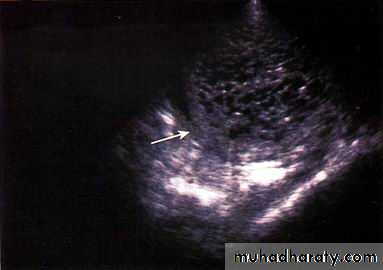

Quantitative beta-HCGUltrasound is the criterion standard for identifying both complete and partial molar pregnancies. The classic image is of a “snowstorm” pattern

A sonographic findings of a molar pregnancy. The characteristic “snowstorm” pattern is evident.

Transvaginal sonogram demonstrating the “ snow storm” appearance.